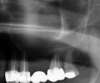

Cas 1: Le comblement sinusien maxillaire consiste à créer un volume osseux dans le sinus maxillaire pour y ancrer des implants.

Une poudre d’os est placée pour combler le sinus maxillaire et permettre la pose d’implants.

Des membranes de PRF sont placées pour épaissir la muqueuse sinusienne et refermer la fenêtre et recouvrir les implants enfouis. Après l’extraction des prémolaires et molaires maxillaires, un comblement sinusien est nécessaire une fois sur deux pour poser des implants de 10 mm de longueur.

AVANT

APRES